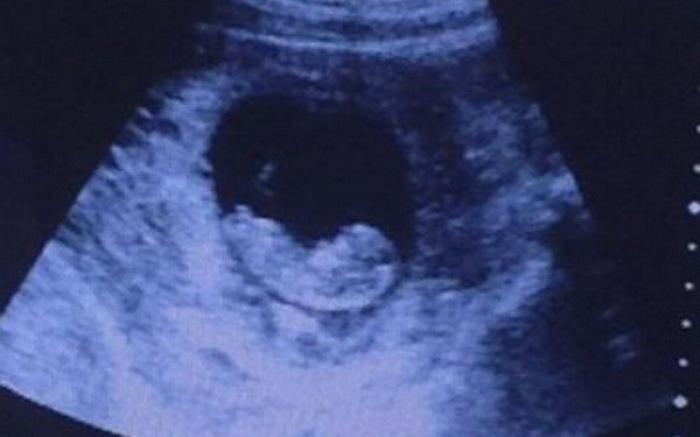

Ecografia care i-a CUTREMURAT pe toţi! Cine veghează asupra copilului nenăscut

La prima vedere, pare doar o ecografie obişnuită a unui copil nenăscut, care se odihneşte liniştit în pântecele mamei sale. Însă dacă te uiţi în dreapta fotografiei e posibil să descoperiţi ceva tulburător. Chipul unei femei a fost zărit de numeroşi internauţi.